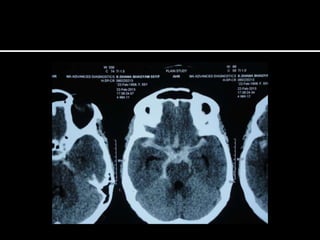

   Sub acute and progressive headache

   New onset >40 yrs of age

   Change in pattern(intensity of pain, frequency of

attacks, new features, decreased response to treatment)

   Association : nausea or vomiting not explained by migraine

or systemic illness ; nocturnal occurrence or morning

awakening; precipitation or worsening by changes in posture

or Valsalva maneuver; confusion, seizures, weakness

   Abnormalities on neuro.examination